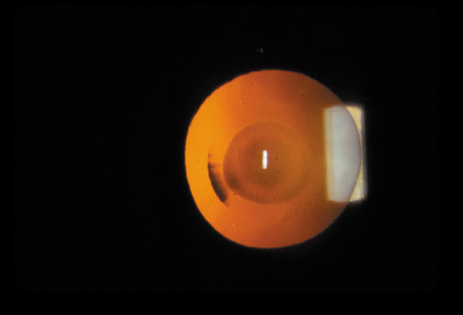

The PSC is the least prevalent subtype in most population-based studies.18 These cataracts often occur in combination with nuclear or cortical cataracts in the later stages. They are easily noticed on retroillumination because they are usually located centrally, and may interfere with funduscopy (Fig. 12). In early stages, patients usually complain of subjective symptoms such as glare disability32 and difficulty focusing on near objects. This is because when the pupil constricts during accommodation, the light entering the eye becomes concentrated centrally, where the PSC is also located. This causes light scattering and interferes with the ability of the eye to focus an image on the macula. In addition, these opacities lie at or near the nodal point of the eye, further interfering with focusing of the image on the macula.

Fig. 12. PSC. Note the central location, which gives rise to severe glare disability.

One can examine this type of cataract with direct illumination, using the narrow and broad beams of the slit-lamp to show the characteristic granular inner surface immediately in front of the posterior capsule (Fig. 13). The problem with this technique, however, is that patients may not tolerate any prolonged direct illumination because of the glare. Retroillumination is therefore more useful for revealing the outline of the opacity, since it is usually seen as an “island” in the center of the posterior capsule, which is further highlighted by the shadow cast by the opacities.33 However, in the early stages of this type of cataract, the dust-like particles that might be noticeable in the central posterior subcapsular area with direct illumination disappear or are difficult to see with retroillumination (Fig. 14). Eventually this “dusting” becomes dense enough to cast a shadow and thus appear on retroillumination. The smooth orange background of the fundus helps to highlight the rough, irregular pseudopodia-like edges of the central opacity. In advanced stages, the PSC may become a thick, calcified plaque (Fig. 15). During surgery, excessively vigorous scraping or vacuuming of the calcified opacity can lead to rupture of the posterior capsule. Usually, small remnants that are left behind after surgery are reabsorbed and do not interfere with vision; otherwise, they are easily treated with a neodymium : yttrium (Nd:YAG) aluminum garnet laser. Pathologic evidence suggests that most PSCs result from the migration of bow region cells into the potential space (along with accumulated cellular debris) between the posterior capsule and the cortex.34–36